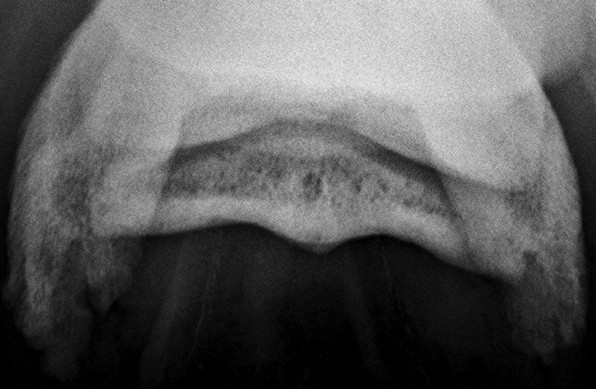

A másik nyírcsont felvétel, a skyline. Úgy készül, hogy a lovat ráléptetjük a kazettára. A nyilak mutatják a csont helyeződését.

Normális nyírcsont. Jól elkülönülő vékony, fehér kéregállomány és sötétszürke velőállomány, benne vékony csatornácskák.